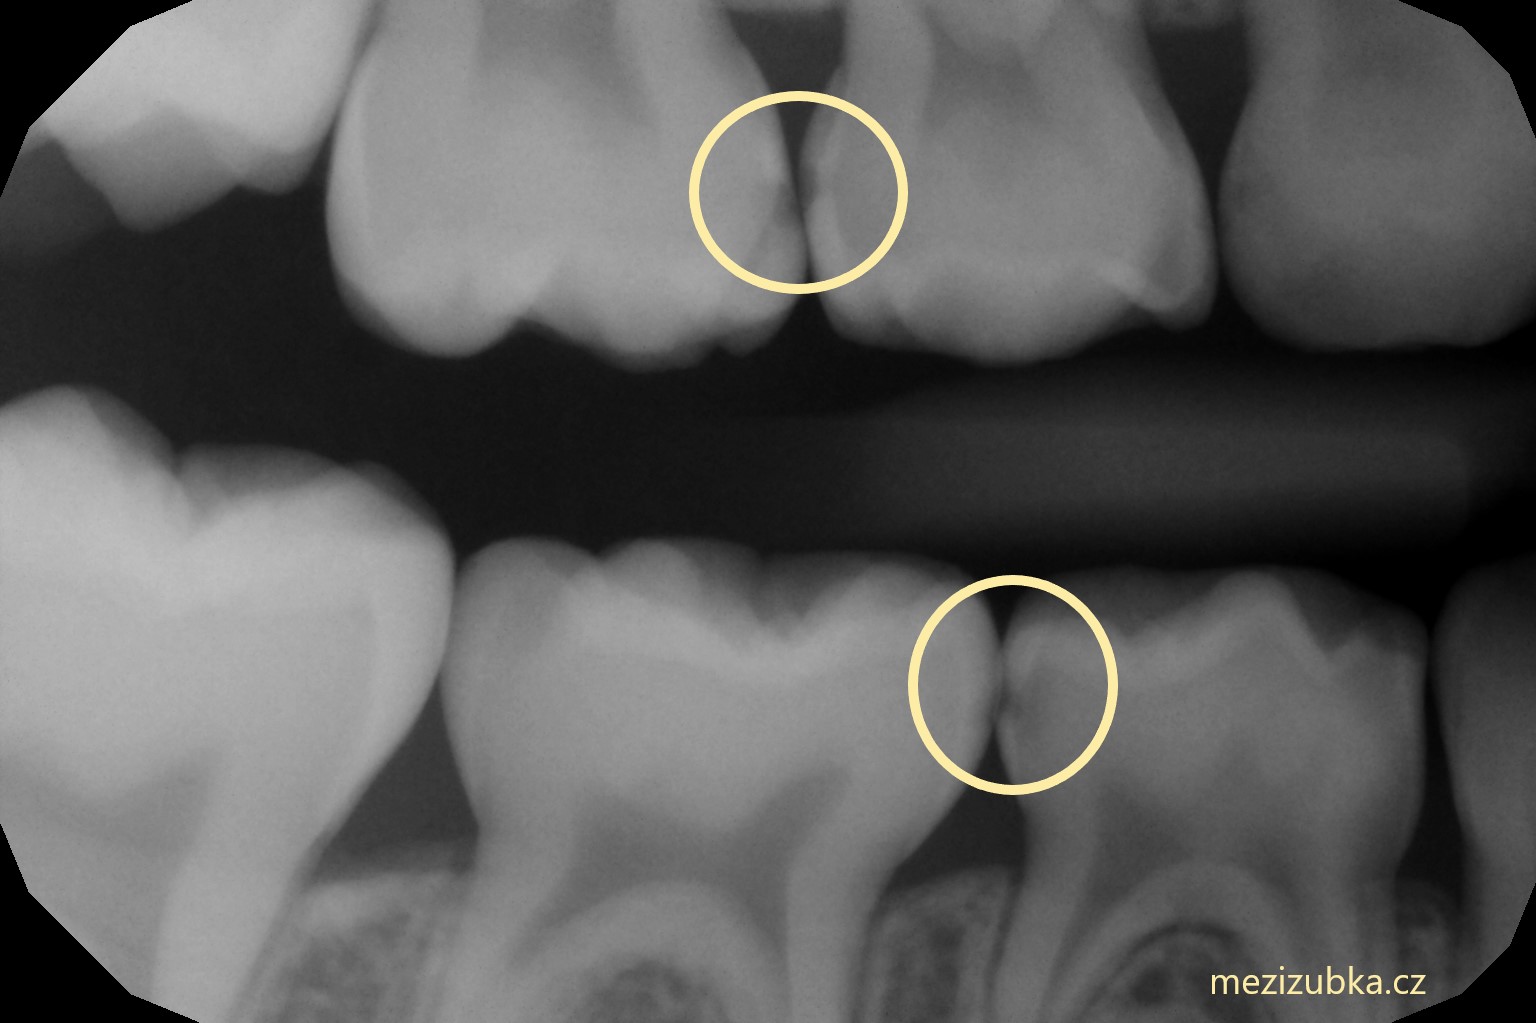

V čem je mezizubní kaz tak zákeřný?

- Není vidět pouhým okem. S jeho diagnostikou nám může pomoci speciální röntgenový snímek, tzv. BITEWING, mezi 4. – 5.rokem.